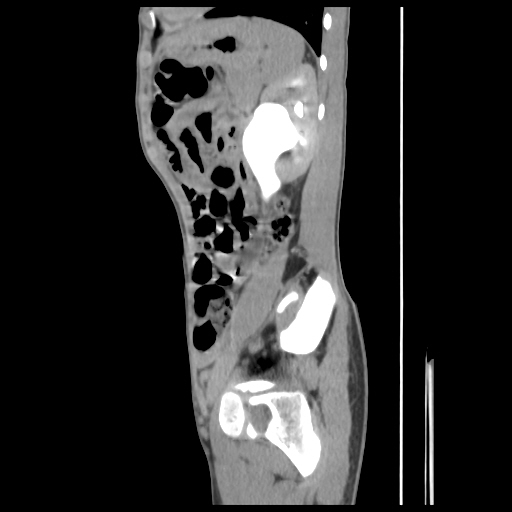

current CT images: